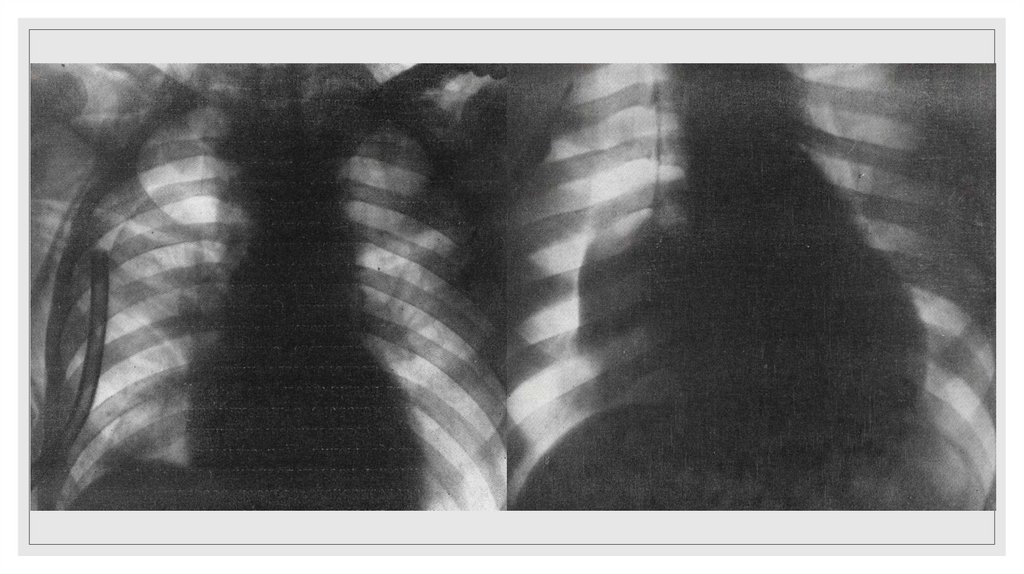

Повреждение грудного отдела аорты

25. Рентгенодиагностика переломов ребер основывается на определении линии перелома и смещении отломков. Косвенным признаком

повреждения ребер является

наличие параплевральной гематомы, имеющей полуовальную форму и

располагающейся вдоль внутренней поверхности ребер на уровне их повреждений

или несколько ниже.

◦ Важно помнить, что на стандартных прямых рентгенограммах видны ребра до VIII

включительно.

◦ Переломы нижних ребер могут сочетаться с повреждением органов брюшной

полости (печень, селезенка).

◦ Чаще всего на стандартных прямых рентгенограммах не диагностируются

переломы боковых отрезков без смещения отломков либо с незначительным

смещением отломков.

◦ Необходимо тщательно изучать не только ребра, но остальные кости (ключицы,

лопатки, позвоночник, а так же грудину)